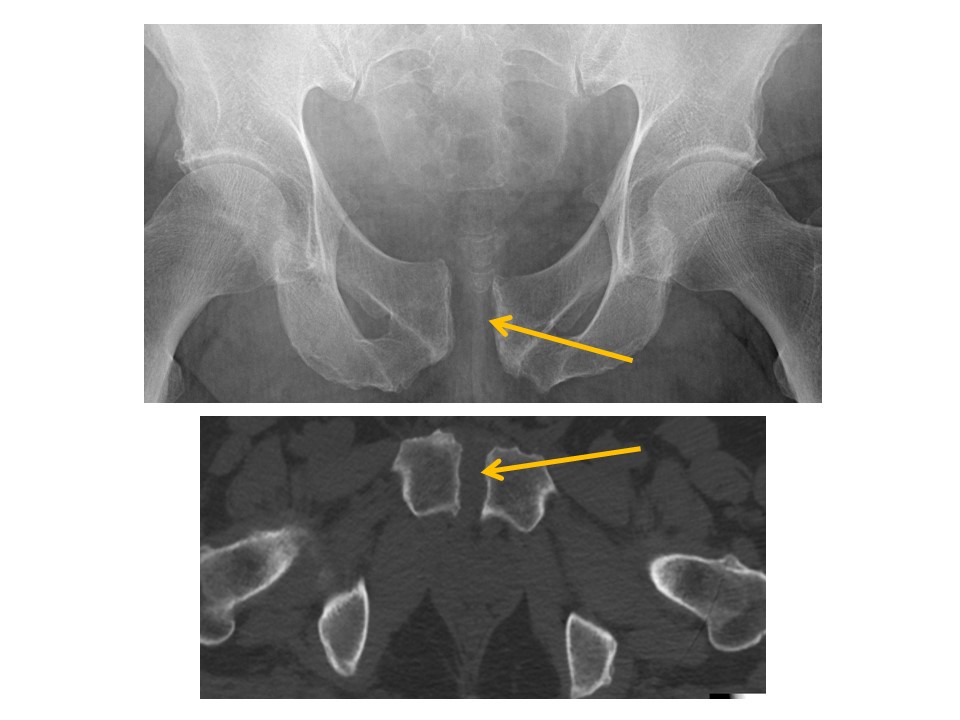

PUBIC SYMPHYSIS and RAMI

There is a pubic ramus fracture. [Yes/No]

HIPS/PROXIMAL FEMURS

Acetabular roofs are discontinuous. [Yes/No]